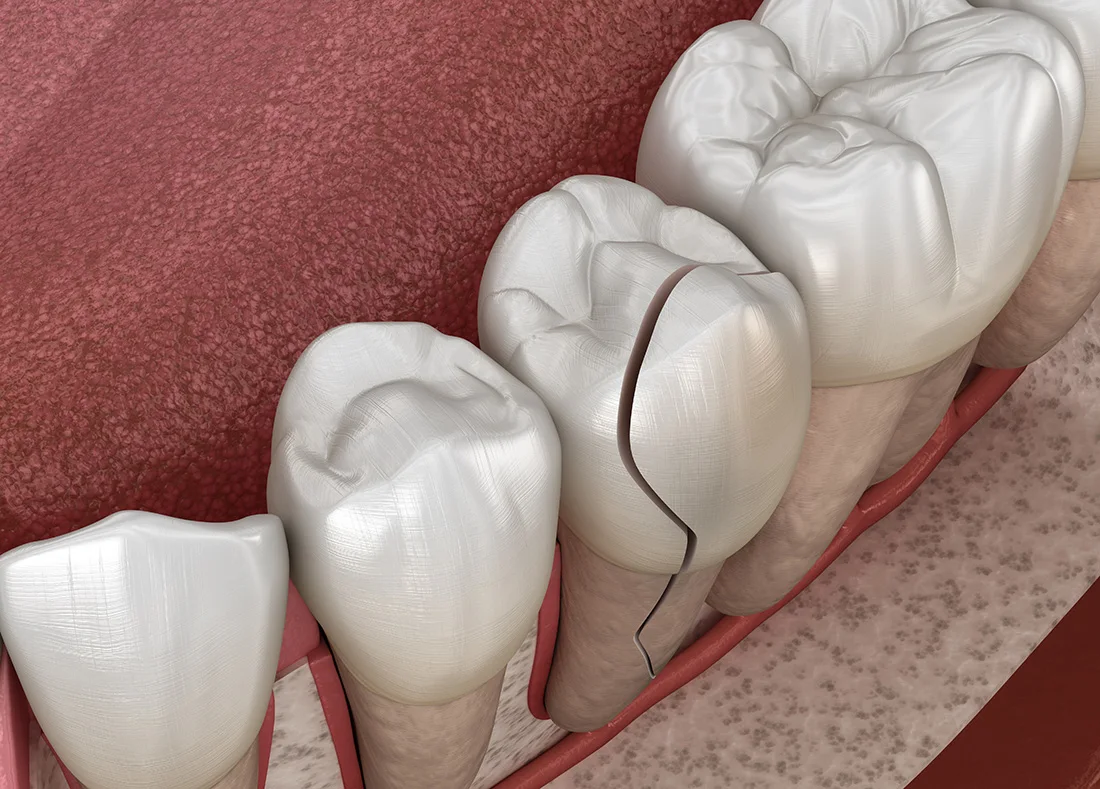

Prevent Bigger Problems

Left untreated, small dental issues can lead to serious complications. Emergency care stops problems before they escalate.